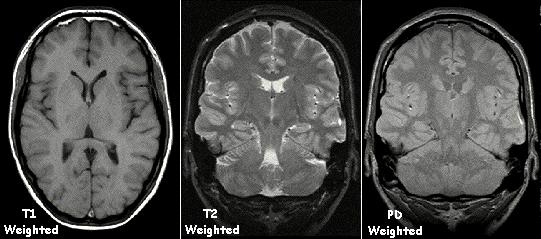

In the late 1970s, physicists Peter Mansfield and Paul Lauterbur introduced an MRI-related technique, like the echo-planar imaging (EPI) technique [6]. Then in 1971 at Stony Brook University, Paul Lauterbur applied magnetic field gradients in all three dimensions and a back-projection technique to create NMR images and published the first images of two tubes of water in the journal Nature [7]. The non-invasive medical imaging procedure known as magnetic resonance imaging (MRI) creates detailed images of your body’s organs and tissues by combining radio waves generated by a computer and a magnetic field. An MRI machine may detect water molecules inside a body when it is placed into the machine. Water is distributed all over the body. MRI machines can differentiate and construct an image by passing radio waves throughout the body. MRI provides better quality images compared to CT scans for the diagnosis of a disease. Figure 3 represents an MRI-scanned image.